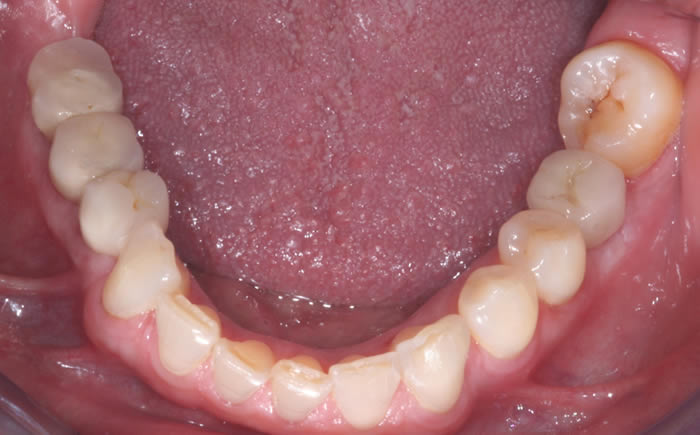

More back teeth replaced by dental implants

Case Three (2 images)

Case Four (4 images)

Case Five (4 images)

Case Six (8 images)

Case Seven (4 images)